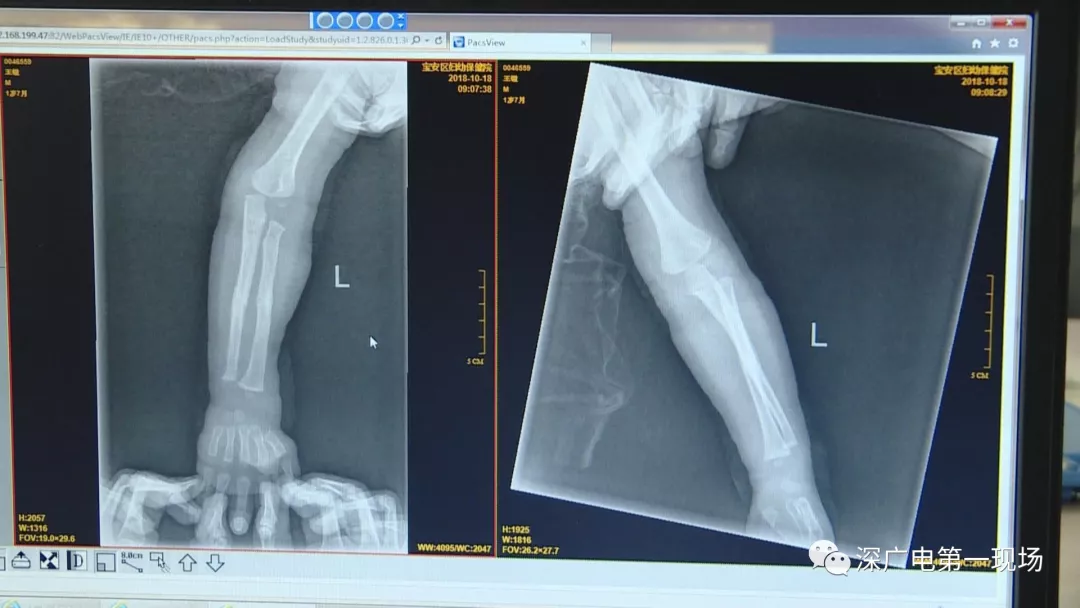

因禍得福!1歲男童摔傷送院 醫(yī)生竟從胸片中發(fā)現(xiàn)了這個(gè)…

胳膊摔骨折胸片里發(fā)現(xiàn)異物